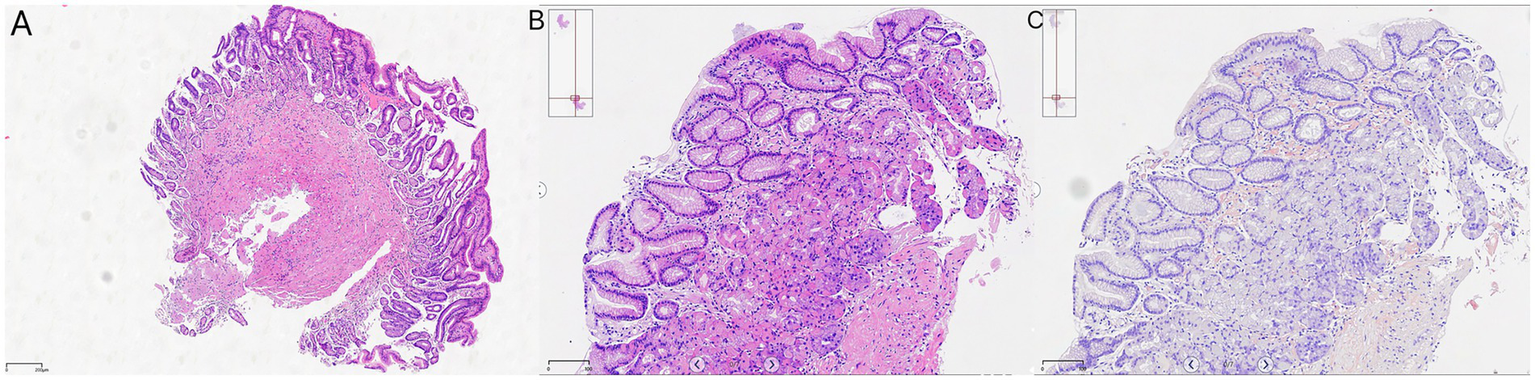

On 10 April 2025, the patient underwent repeat endoscopy due to new-onset gastroesophageal reflux symptoms. The endoscopy revealed disc- and linear-shaped erythema in the gastric body with abnormally bright reddish coloration (Figures 2A–D). A submucosal tumor (SMT)-like protrusion was observed in the posterior wall of the lower gastric body (Figure 2E). In contrast, the gastric antrum showed no visible erythema (Figure 2F). Biopsy samples from these lesions showed eosinophilic deposits in the lamina propria (Figure 3B). Congo red staining was weakly positive, and apple-green birefringence under polarized light confirmed amyloid deposition (Figure 3C). Retrospective review of the 2023 biopsy revealed previously overlooked eosinophilic deposits (Figure 3A).

Figure 3

Histopathology: (A) 2023 antral biopsy (hematoxylin & eosin [H&E], ×40 magnification); (B) 2025 gastric body (H&E, ×40 magnification); and (C) Congo red staining with birefringence under polarized light, ×40 magnification.

Upon retrospective analysis of the patient’s gastric biopsy from 2023, we identified small eosinophilic deposits in the muscularis mucosae that had initially been overlooked. This misdiagnosis can be attributed to both clinical sampling and pathological interpretation limitations (18). The biopsy was not obtained from the most prominent erythematous areas observed during endoscopy, where amyloid deposits were likely concentrated. Additionally, the pathologist did not suspect amyloidosis at the time, and the small eosinophilic deposits were misinterpreted as fibrous tissue or non-specific exudates. This case highlights the need for improved collaboration between clinicians and pathologists. Clear clinical suspicion of rare diseases such as amyloidosis should be communicated to the pathology team to trigger appropriate diagnostic staining, such as Congo red (19). Furthermore, clinicians should consider deeper or targeted biopsies for patients with persistent, unexplained gastric lesions that do not respond to conventional treatments, especially when common causes have been ruled out. In cases of unexplained gastric erythema, especially when accompanied by other systemic signs, early recognition and biopsy can be pivotal in identifying rare conditions such as GIA.